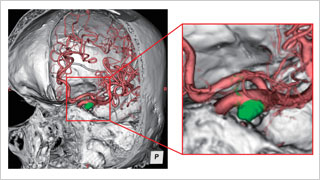

德洲会 名古屋德洲会综合医院 脑神经外科

天野 贵之